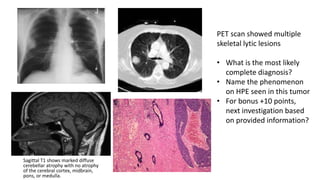

Sagittal T1 shows marked diffuse

cerebellar atrophy with no atrophy

of the cerebral cortex, midbrain,

pons, or medulla.

B

PET scan showed multiple

skeletal lytic lesions

• What is the most likely

complete diagnosis?

• Name the phenomenon

on HPE seen in this tumor

• For bonus +10 points,

next investigation based

on provided information?

Q3 A 65 yearold man presents to the medicine OPD with complaints of dizziness, difficulty in speaking, difficulty swallowing food at dinnertime and a ‘wobbly gait’ since the past 1 month. He also gives a history of weakness in his arms and legs as the day progresses which improves with some activity. He has 50 pack year smoking history. On examination his vitals are stable. On neurological examination there is horizontal nystagmus bilaterally, he has an ataxic gait and demonstrates past pointing on a finger nose test. Muscle bulk, tone and power are normal in all 4 limbs with normal sensory exam. His CBC reveals mild anemia, leukopenia and leuko- erythroblastic blood picture on PS itself. MRI Brain, CECT chest and Pathology findings from CT guided biopsy are shown

Sagittal T1 showsmarked diffuse cerebellar atrophy with no atrophy of the cerebral cortex, midbrain, pons, or medulla. B B PET scan showed multiple skeletal lytic lesions • What is the most likely complete diagnosis? • Name the phenomenon on HPE seen in this tumor • For bonus +10 points, next investigation based on provided information?